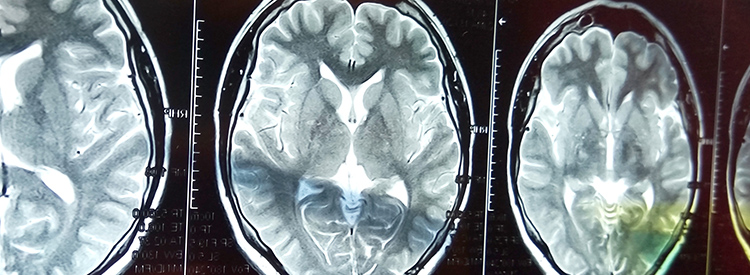

當大腦部分血流被切斷時,就會發(fā)生中風。當這種情況發(fā)生時,失去血液供應的腦組織就會受傷或死亡。根據大腦受損區(qū)域控制的功能,這會導致身體功能喪失。例如,如果控制左臂運動的區(qū)域受損,該臂就會變得虛弱或癱瘓。如果左臂控制感覺的區(qū)域也受到影響,手臂會麻木,或者也可能有燒灼感或疼痛感。由于大腦控制著我們所有的運動和感覺,包括視覺和言語,因此幾乎任何事物都可能受到中風的影響。

中風治療進展緩慢。如果在最初幾分鐘內進行治療,可以在急診室或醫(yī)院使用特殊藥物(阿替普酶或組織纖溶酶原激活劑)來逆轉或限制缺血性中風造成的損害。這種藥物可以分解阻塞血管的凝塊。如果在最初的幾分鐘到幾小時內使用,可以避免或限制對大腦的任何損害。在使用阿替普酶之前,必須進行 CT 成像來確定中風類型,以確認中風不是出血性的。由于阿替普酶會分解血栓,因此如果用于出血性中風,可能會導致嚴重惡化或死亡。有時會治療出血性中風以避免進一步出血。